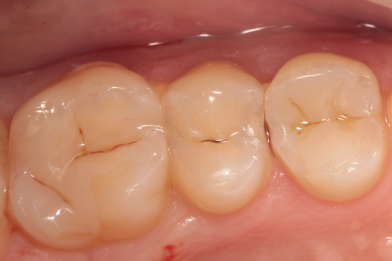

Пациент обратился с жалобами на боли во время приема пищи. После обследования была выявлена устаревшая пломба с дефектом на жевательном

Бояринов Сергей Эдуардович

зубе. Произведено лечение: снятие старой пломбы с последующим восстановлением анатомо-физиологический формы при помощи пломбировочного материала. -